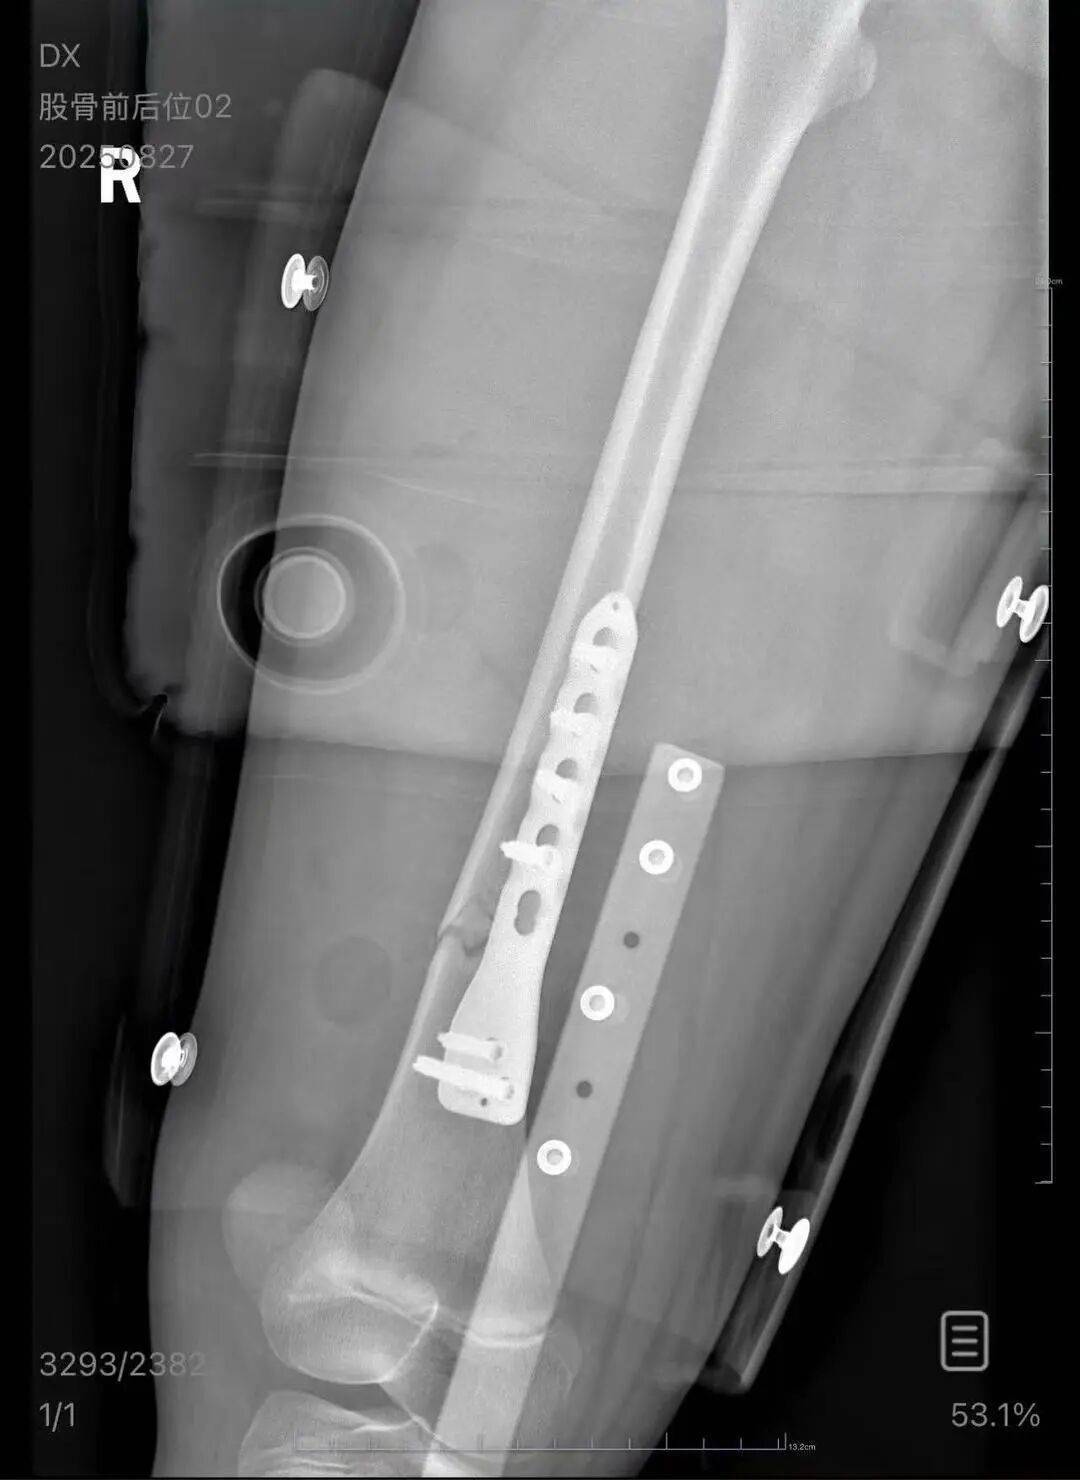

▲朱女士女儿手术后拍的X光片 受访者供图

朱女士向记者出示的医院病历显示,8月24日凌晨,朱女士的女儿到医院就诊加密货币。医院诊断朱女士的女儿右股骨骨折,需要住院进一步治疗。